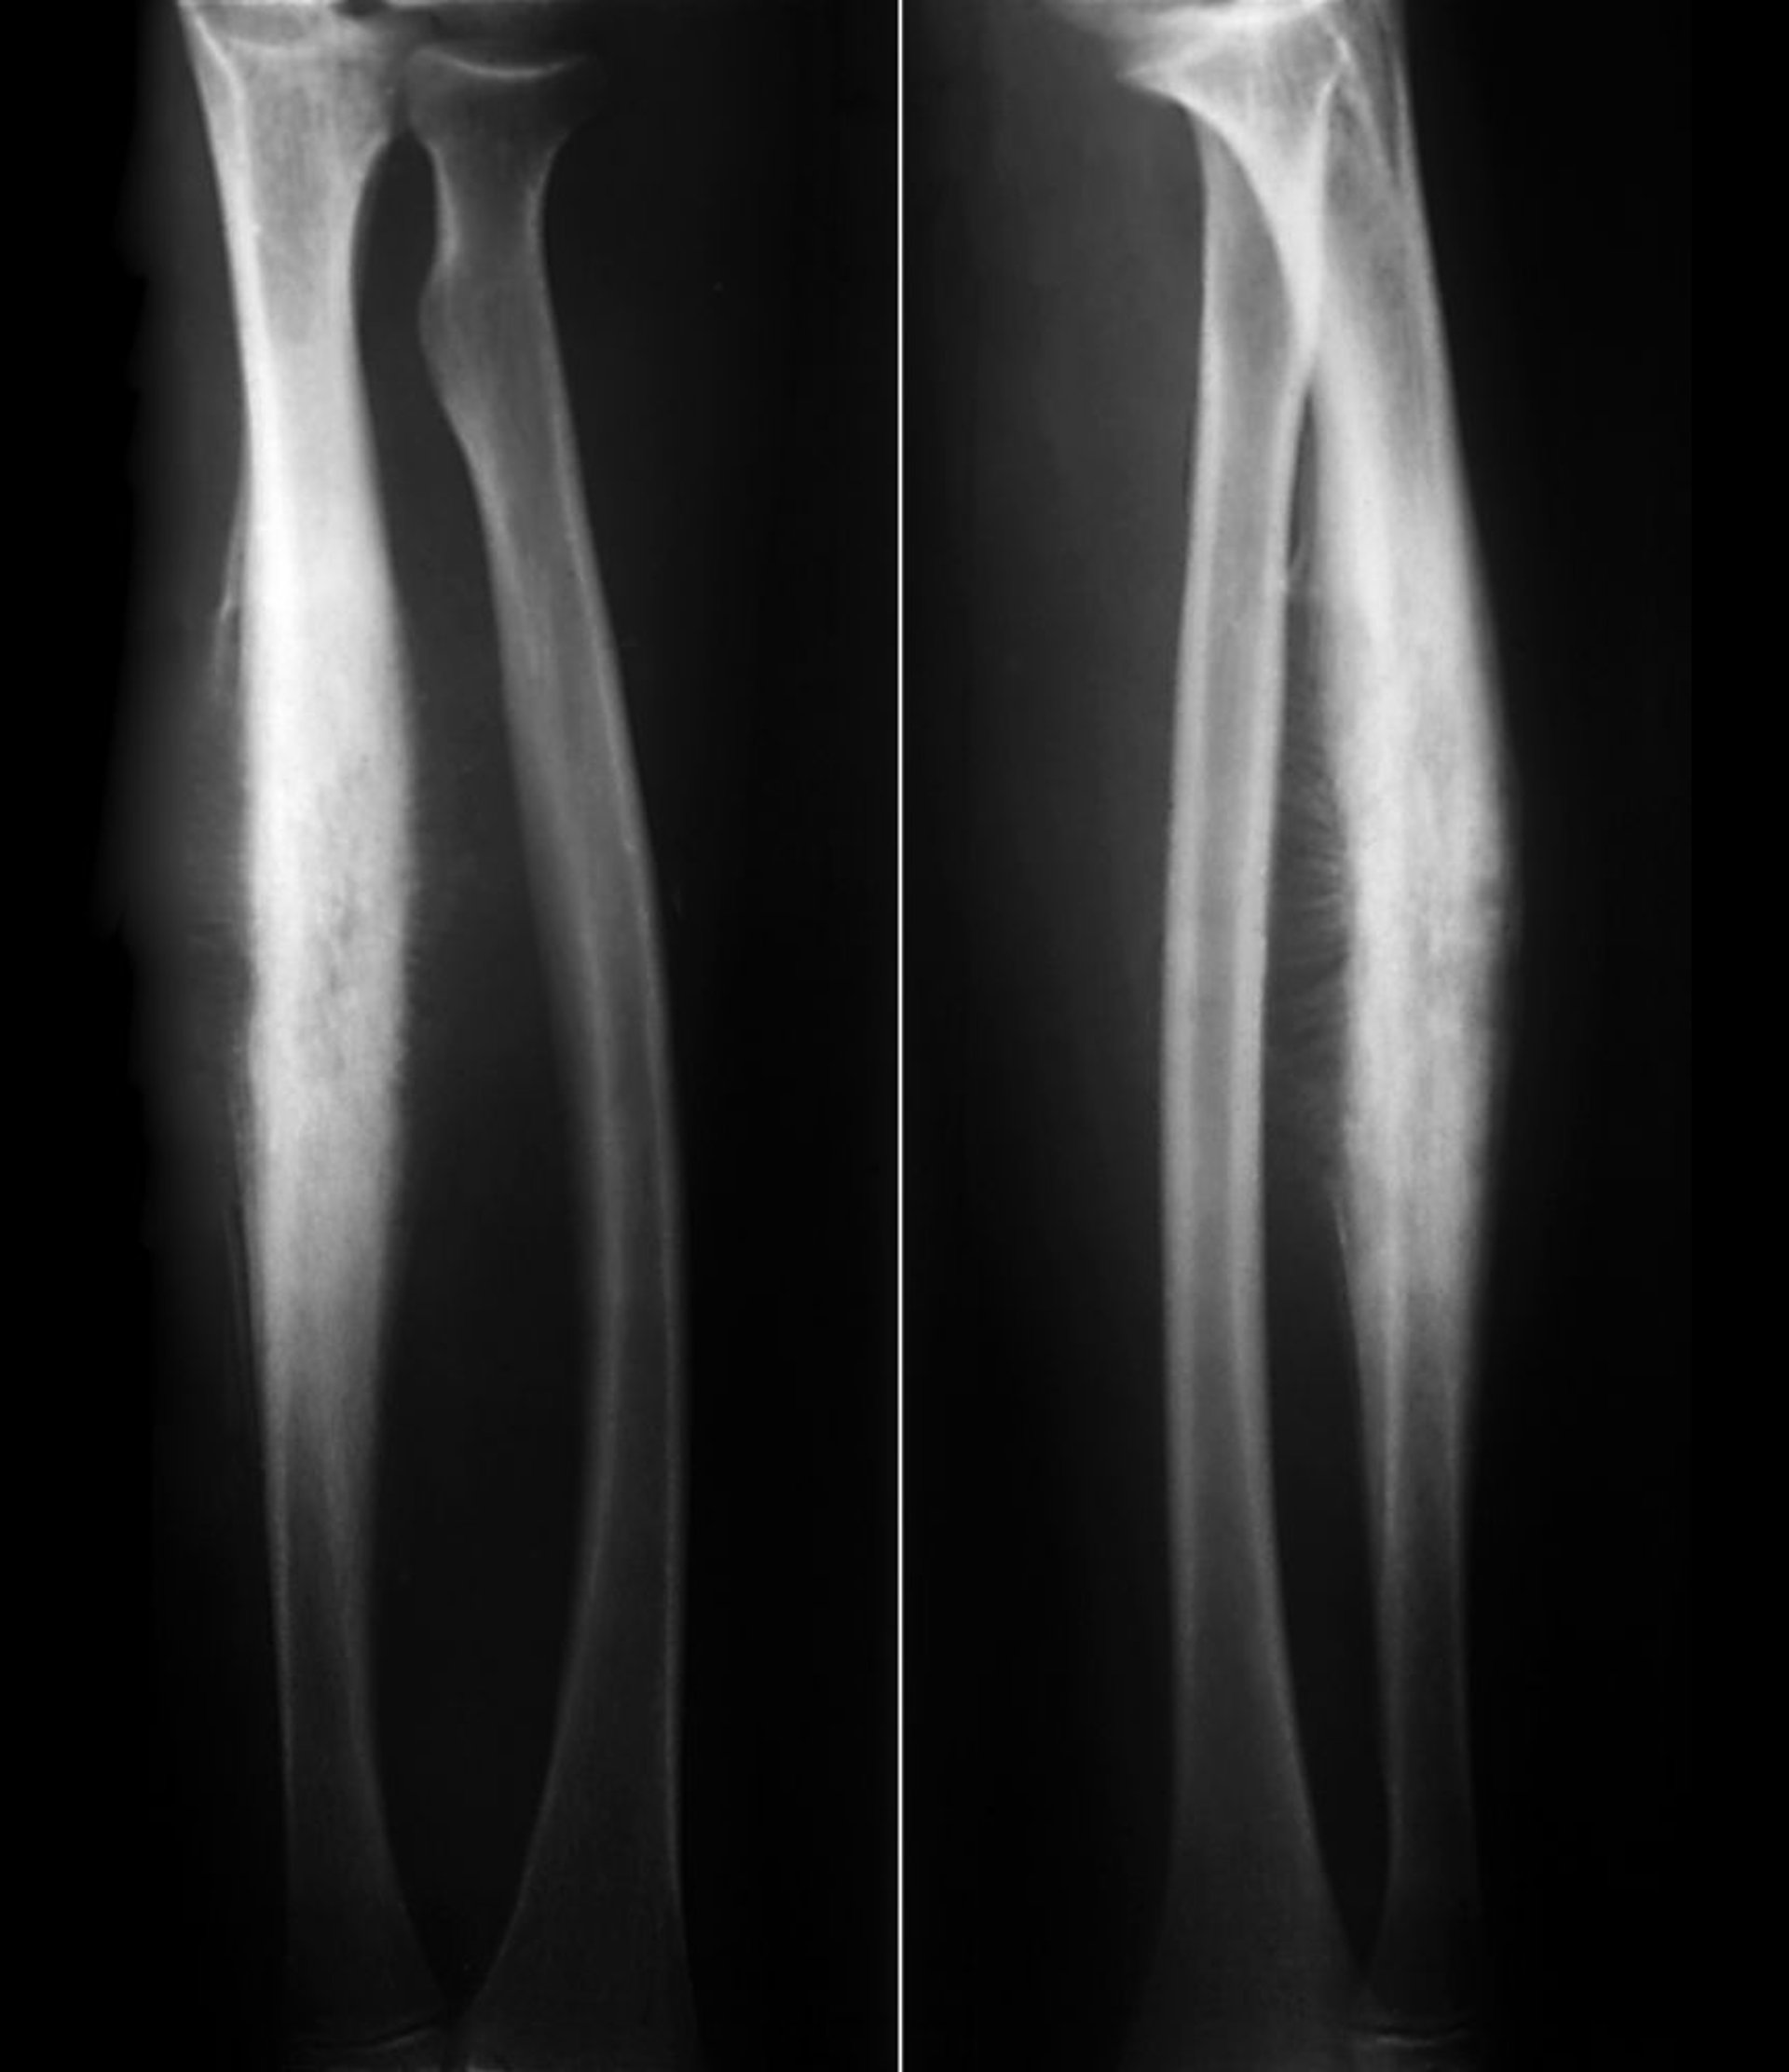

Саркома Юинга лучевой кости

При саркоме Юинга в области диафиза лучевой кости отмечается субпериостальное образование новой костной ткани с характерной периостальной реакцией типа «солнечных лучей»» (sunburst), а также литическое разрушение кортикального слоя кости.